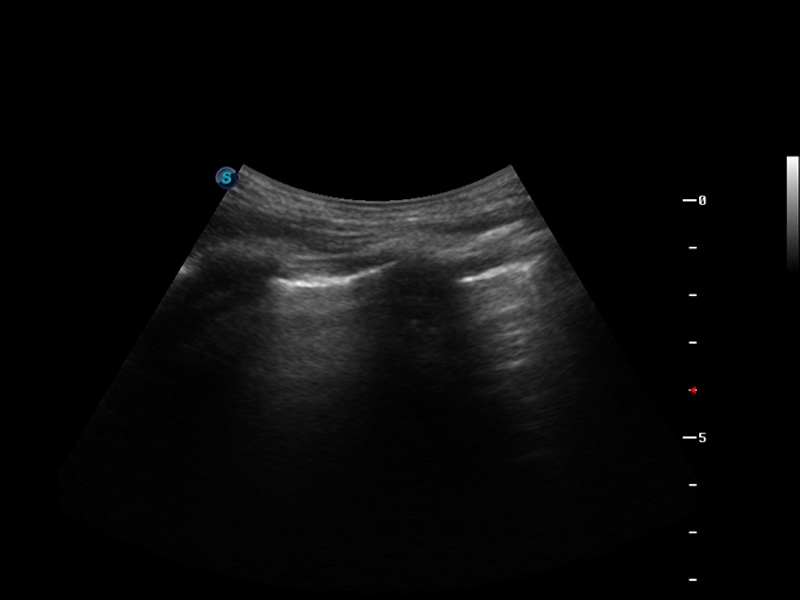

S9便携式彩色多普勒超声诊断仪是16877太阳集团研发的高端便携彩超设备,外观设计新颖、产品性能卓越。S9在便携超声领域采用了突破传统的触摸屏交互设计,并以先进的软件硬件技术和设计理念,为您带来清晰的图像质量、稳定的工作性能和便捷的操作体验。

μ-Scan微米成像